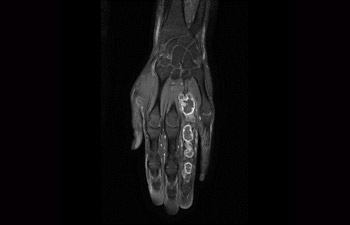

Ingenia Elition fornisce un'eccellente qualità delle immagini ed esegue esami RM a una velocità fino al 50% più elevata¹.

Velocità applicata sempre e correttamente.